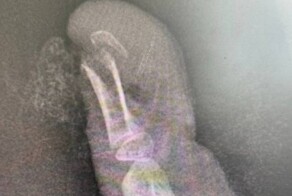

Из-за механизма травматического отчленения операция была сложной и длилась почти 13 часов: три ампутированных пальца были реплантированы полностью, а мизинец ввиду дополнительных повреждений мягких тканей восстановить не представлялось возможным.

Операция была разделена на два этапа. Во время травматологического этапа выполнен остеосинтез костей фаланг пальцев, восстановление сухожилий разгибателей и сгибателей пальцев. Во время микрохирургического этапа восстановили вены и артерии, обеспечивающие кровообращение, а также восстановили пальцевые нервы, которые обеспечат возвращение чувствительности в более отдаленном периоде.

Послеоперационный период протекал стандартно, без осложнений. Реплантированные сегменты прижились полностью, и пациента выписали через 10 дней с момента поступления. Через две недели швы сняли и теперь мужчине предстоит долгая реабилитация.

на фото три пальца.....